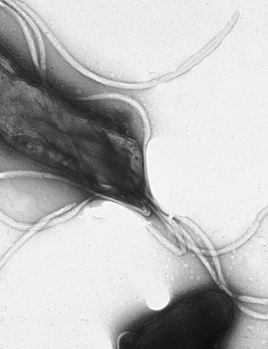

L’infiammazione gastrica rappresenta il primo segnale della presenza del batterio. Come spiega a Libero il Dott. Davide Moioli, specialista in chirurgia generale mini invasiva e bariatrica: “Il meccanismo principale attraverso il quale favorisce lo sviluppo del cancro gastrico è legato alla progressione istopatologica delle lesioni. L’infiammazione cronica indotta dal batterio altera l’equilibrio tra danno e rigenerazione della mucosa, favorendo mutazioni genetiche che portano allo sviluppo delle lesioni precancerose con una precisa sequenza: gastrite cronica, gastrite atrofica, metaplasia intestinale, displasia ed infine adenocarcinoma” .